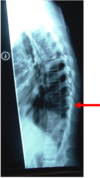

27

hangmans fracture